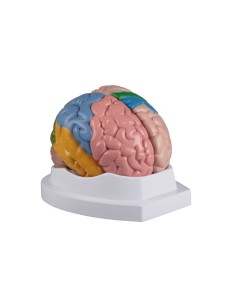

Dal cranio in 22 parti con incastri magnetici ai modelli di colonna vertebrale, da quelli di articolazioni a quelli di cuore, ogni pezzo della nostra collezione è progettato per un’immersione totale nello studio dell’anatomia umana. I nostri modelli, realizzati tramite scansioni di ossa vere, garantiscono un’esperienza tattile autentica e una fedeltà di peso quasi identica agli originali.

Essenziali per studenti e professionisti, i nostri modelli anatomici sono strumenti didattici che permettono di osservare le strutture anatomiche con precisione, eliminando la necessità di dissezioni o studi invasivi. Sono inoltre utili per spiegare ai pazienti le patologie, rendendo la comunicazione più efficace e risparmiando tempo prezioso.